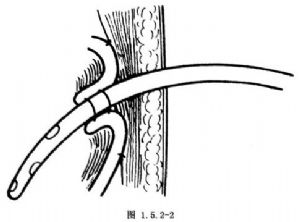

这是最简便的一种暂时性胃造口术。取平卧位,做上腹部中线或左上腹直肌切口。进入腹腔后,将胃体部置于手术野中,一般选择在胃体部前壁胃大弯小弯的中点处造口。用湿纱布垫覆盖于手术野四周,保护腹腔防止污染。用细的不吸收线于预定造口处做一荷包缝合。于荷包缝合的中央切开胃壁全层,切口大小以正好置入导管为度。用F14~16号导尿管或乳胶管经此切口插入胃腔3~5cm,亦可用蕈状导管或带气囊的导管插入,以防脱出。收紧结扎荷包缝合线使浆膜内翻紧贴导管。于第1个荷包缝合线外1~1.5cm处再做一荷包缝合并收紧结扎。必要时可做第3层荷包缝合(图1.5.2-1)。于切口左侧腹壁戳一小口,将导管经此口拖出。造口周围的胃壁与腹壁戳口四周的腹膜固定缝合3或4针,应无张力(图1.5.2-2)。最后将导管固定缝合于皮肤,按层缝合切口(图1.5.2-3)。